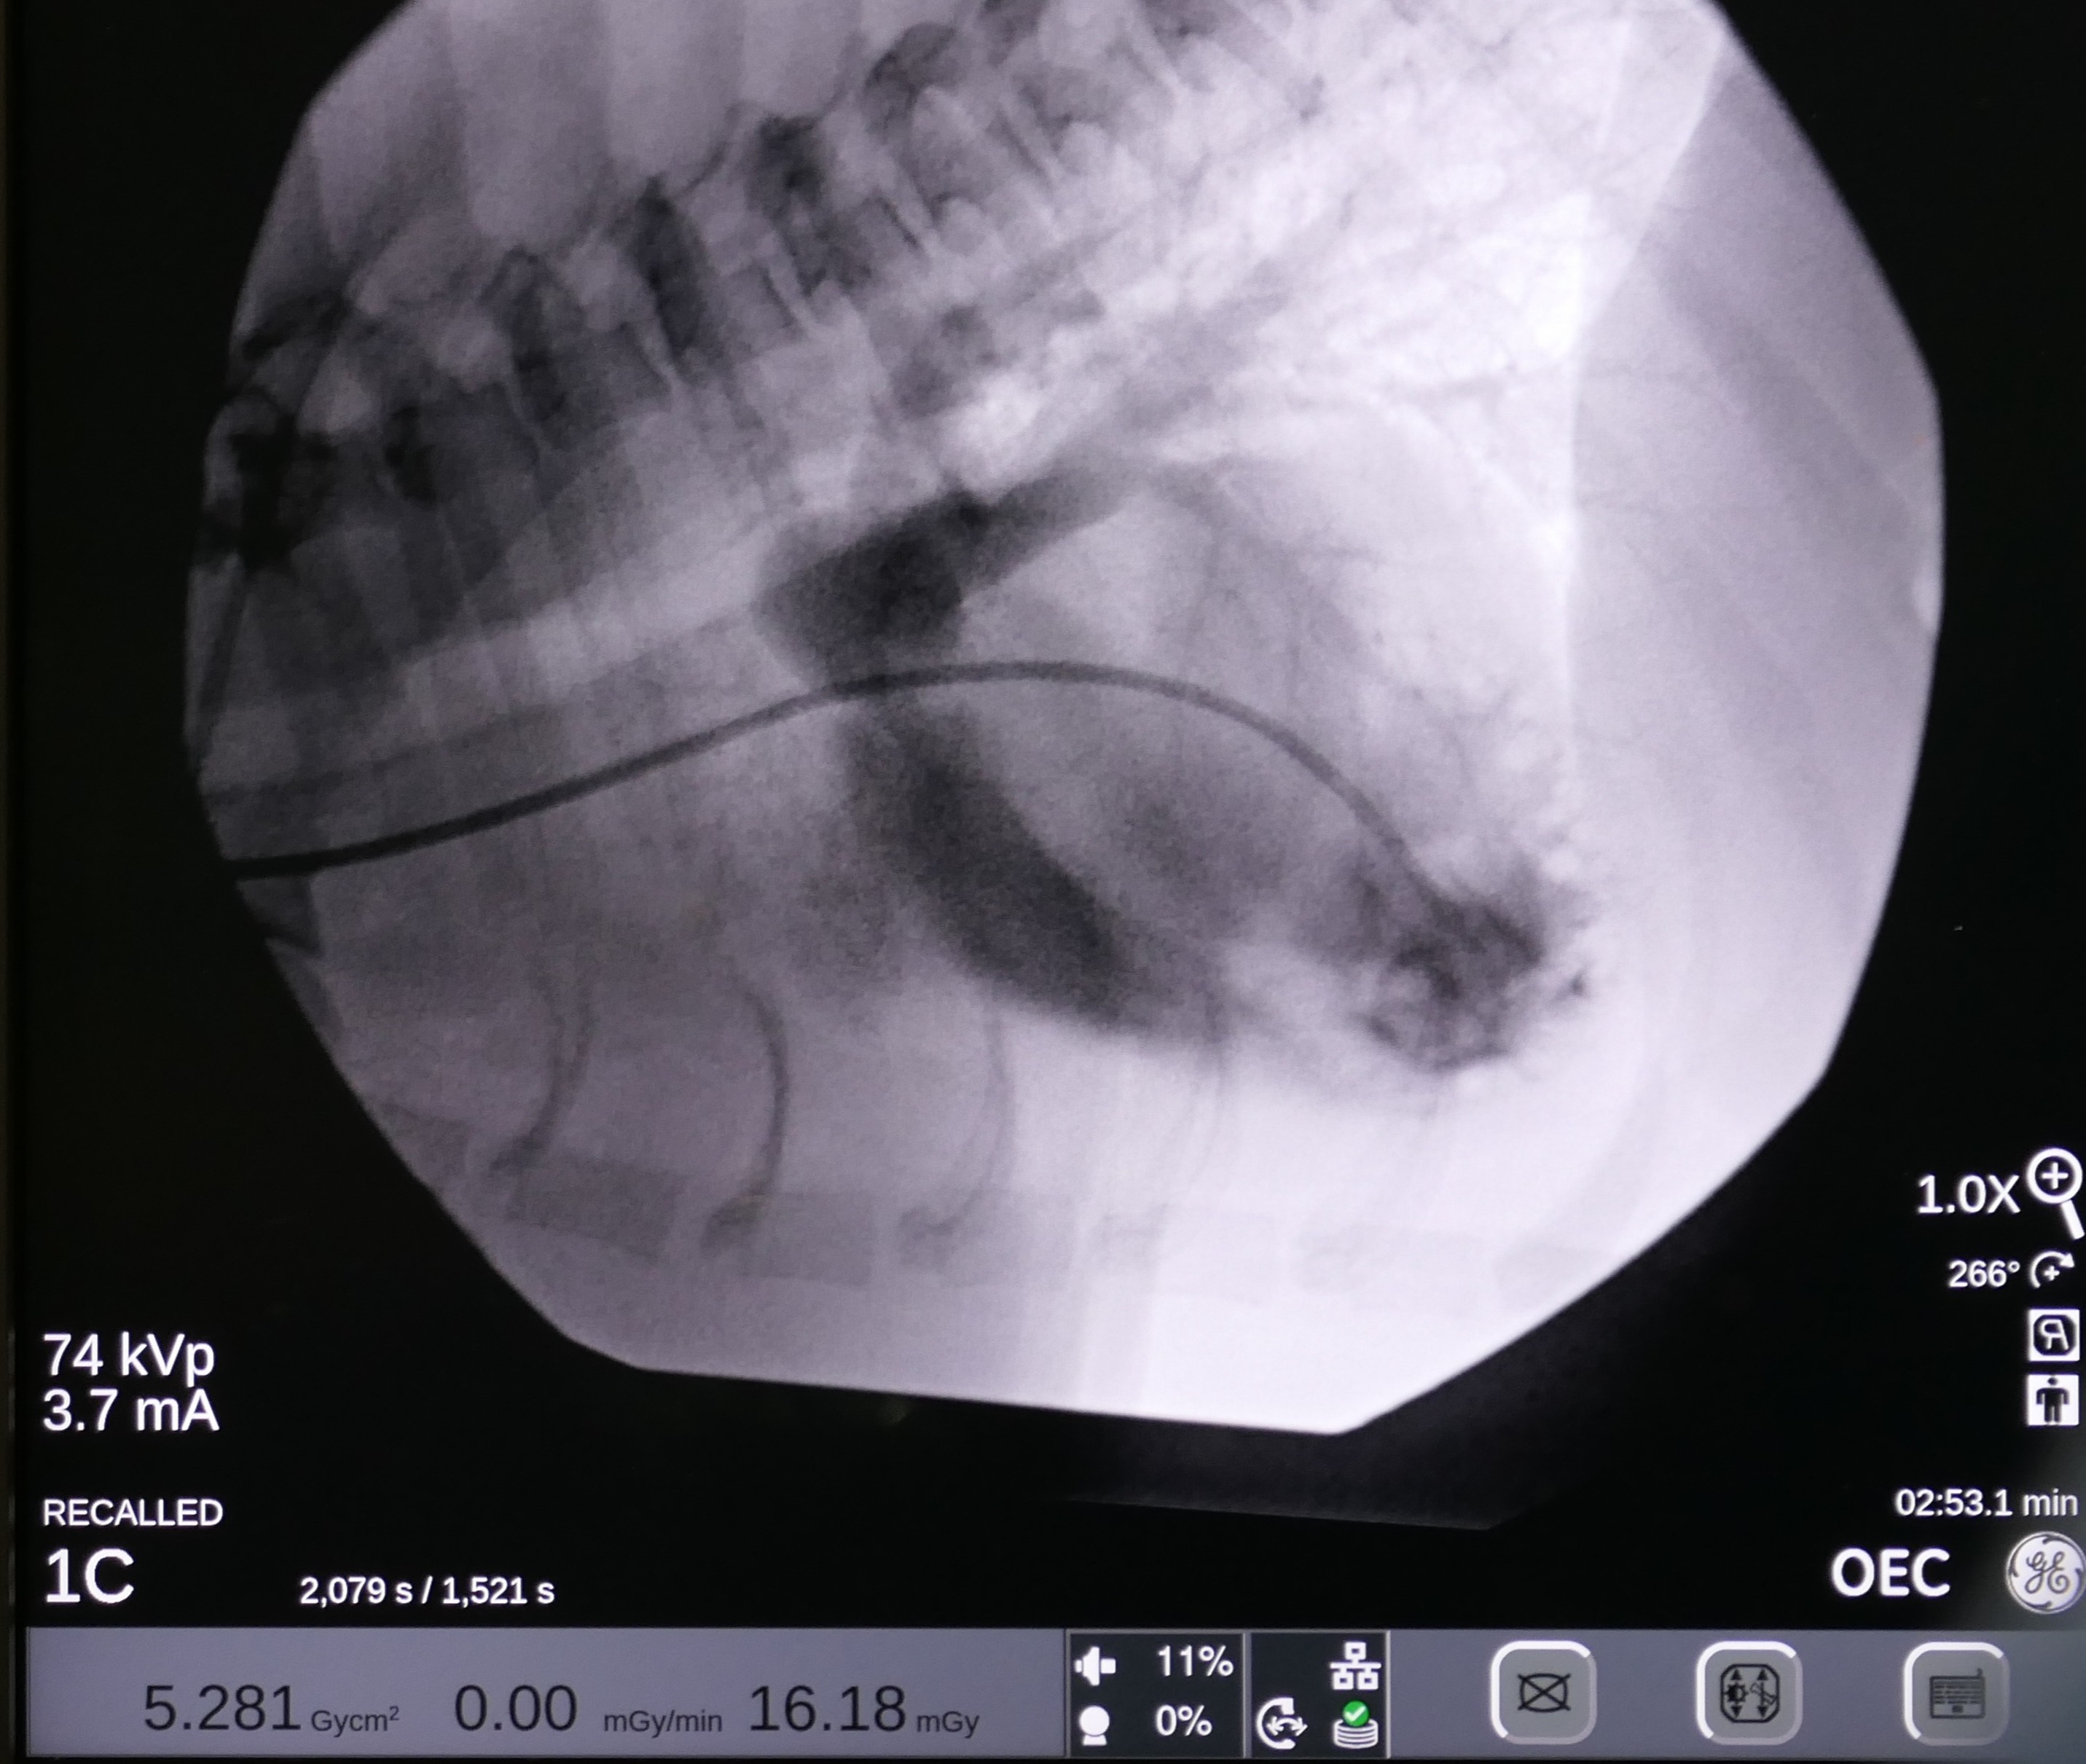

On May 7 2024, Snoop underwent a balloon valvuloplasty at MVRH. The procedure involved placing Snoop under general anesthesia and accessing the affected valve via the external right jugular vein. In order to gain access to the heart, a vascular introducer is first placed into the vein. This allows exchanging various wires and catheters without causing blood loss. Then, using fluoroscopy (Live X-rays) a catheter is advanced into the heart. This catheter has a small air balloon in its tip working as a “sail” and flowing downstream into the heart. Once the anatomy is assessed by using contrast, a Guire is placed to be used as a roadmap. Over this wire, a catheter with a large balloon in its tip is positioned across the fused valves. Once the balloon is inflated, the high pressures reached with this balloon separate the valve leaflets, decreasing the obstruction. This balloon reaches up to 18 atmospheres of pressure, and to put this in perspective, it is the equivalent of roughly stretching it with 260 pounds of force.

Snoop's recovery was uneventful, with a marked decrease in the pressure gradient from 250 mmHg to 80 mmHg. Post-surgery, Snoop was prescribed a recovery regimen including atenolol, gabapentin, trazodone, and amoxicillin/clavulanate potassium to manage pain, sedation, and prevent infection. Owners were advised to monitor Snoop's sleeping respiratory rate and watch for any signs of disease progression, such as coughing or exercise intolerance.